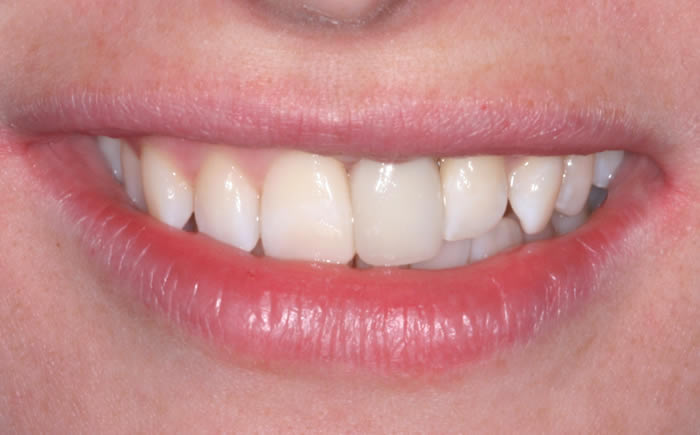

Case Two (4 images)

Missing upper front tooth replaced by dental implant and crown